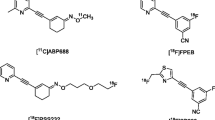

Positron emission tomography (PET) utilizes positron emitter labeled compound to provide valuable information about the target availability under normal and pathological conditions, and then allow evaluating drug intervention. PET can be used to quantify the receptors, transporters, or enzymes expressed at the level of nanomolar concentration in the living tissues. No PET tracer targeting mGluR’s orthosteric sites has been developed, since the high concentration of endogenous glutamate would dramatically compete with very low mass concentration of PET radiotracer23. Hence, several radiotracers targeting mGluR5 allosteric binding sites have been proposed to investigate in vivo glutamate neurotransmission by PET. The first suitable tracer for both preclinical and clinical use, namely [11C]ABP688, was developed in 200624. Despite its favorable characteristics, its major limitation remains the short half-life of its radioisotope (about 20 min), limiting its use to centers with a cyclotron on site. Therefore, and to get around this drawback, two fluorinated radiotracers have recently been developed: [18F]PSS232 and [18F]FPEB. [18F]FPEB (3-[(18)F]fluoro-5-(2-pyridinylethynyl)benzonitrile) is a negative modulator of the mGluR5 allosteric sites with an excellent pharmacological profile with a human mGluR5 Ca2+ Ic50 flux of 0.66 nM, a Ki in rats of 0.20 nM, and a logP value of 2.825. Thanks to its favorable reversible kinetics, a high specificity, and the absence of brain radiometabolites26, [18F]FPEB has been widely used to study in vivo dysfunctional glutamate transmission associated with neuropsychiatric including Parkinson’s disease (PD)27, major depressive disorder28, addictions (alcohol)29, and autism30.